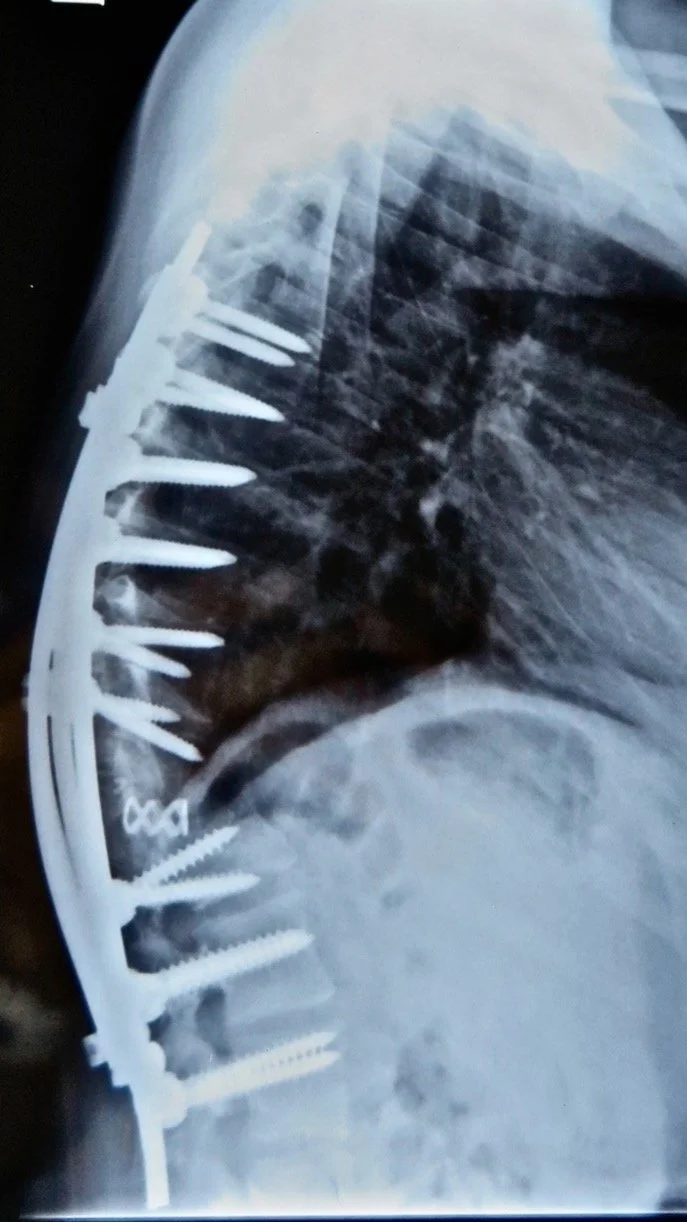

He heard my story, took photos and sent me for x-rays. I came back with my results and he was amazed to see my x-ray – I learned that I had congenital disease (not TB) and that  it curved 246 degrees! They told me to come back in few weeks when Dr Boachie-Adjei, the spine surgeon, comes from Ghana to visit patients. I showed up on my appointment. Dr. Boachie put me on the top priority list for surgery. Dr. Rick’s team started getting me ready for surgery with passport, MRI, CT, visa and tickets. In few months, I flew to Accra, Ghana for life-changing surgery along with other patients.

After 6 months of traction, I had surgery. When they showed me my back right after I got out of the ICU, I got into tears. I have never been that happy. I feel myself being filled with all positive things in the world. I was truly happy! I always had insecurity that I will never get married, but that day, I knew I will get married and have my own life. I recovered and returned home.